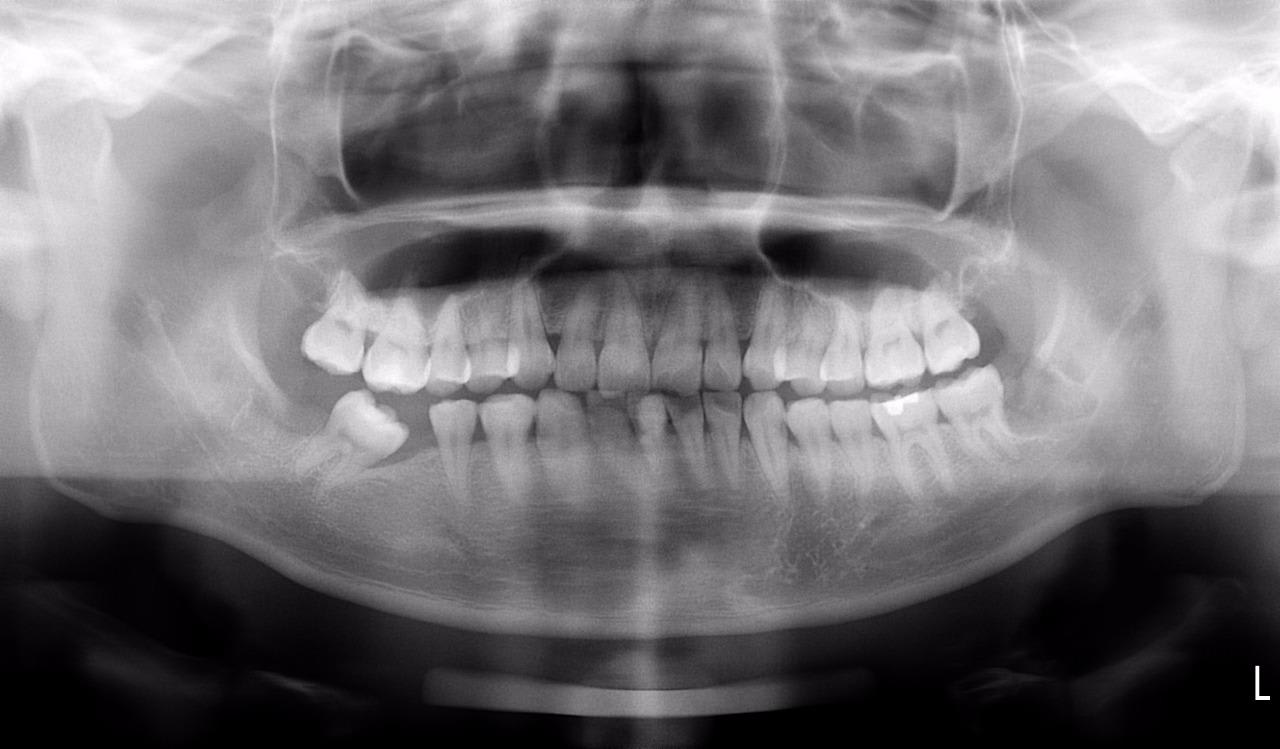

Ici le patient à besoin d'un traitement complet mais j'ai un soucie, la 46 est absente et la 47 versé et à une rotation.

Si je bague haut et bas, je vais être bloqué par le bas qui va prendre plus de temps pour finir la phase d'alignement que le haut. Plus j'aimerais que le patient pose son implant ASAP car sa va faciliter mon travail pour la phase inter arch.

Je prévois deux trois mois grand max pour ouvrir suffisamment l'espace pour permettre la mise en place de l'implant.

Une fois l'implant posé, dépose du système , et trois mois plus tard après l 'ostéointégration poste des bague haut et bas et le traitement se déroulera comme un traitement classique.

En aparté le patient aura plus que probablement un défaut paro sur la 47